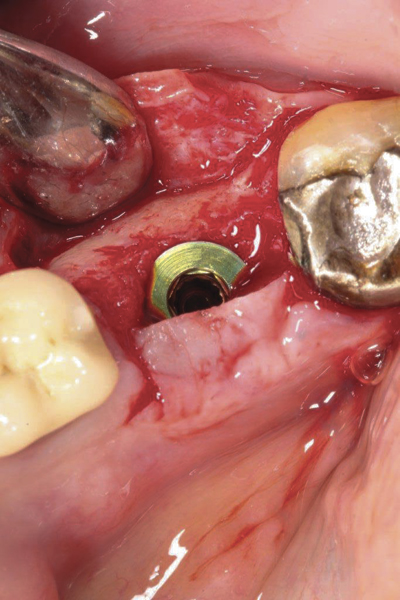

Fig 20. (Case 4) Radiograph of tooth No. 30, which had a hopeless prognosis.

Figure 20

Fig 21. Radiograph of extraction socket. Buccal plate was two-thirds resorbed.

Figure 21

Fig 22. Bone graft was placed in the socket and a d-PTFE barrier was used to cover the graft. The bone graft material was placed beyond the alveolar housing to accommodate shrinkage of graft material and to facilitate attaining a wide alveolar ridge. The barrier was removed after 5 weeks.

Figure 22

Fig 23. Implant inserted in a regenerated ridge after 6 months healing.

Figure 23